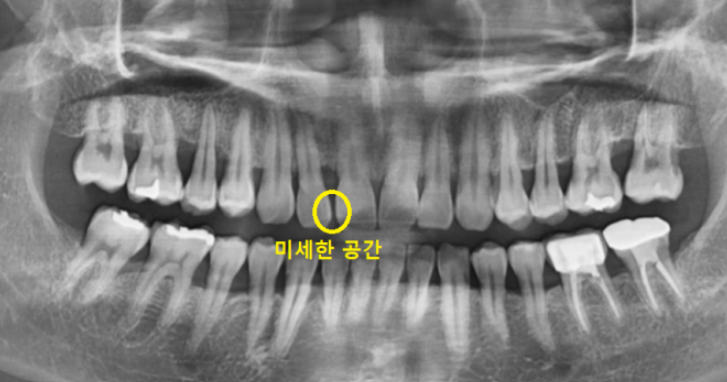

방문해주신 환자분의 경우에도

미세하지만 앞니 사이 공간이 있었습니다.

작은 틈새이지만

공간이 있어서 떼우고 싶다고 하셨습니다.

아무래도 반대편 치아의 경우

붙어있어서 더 비교가 되셨나봐요~

반대편 치아만 해도 잘 붙어있는데

유독 윗니 앞 부분 치아만 틈이 있네요~

오늘 환자분의 경우

옆 치아와의 공간이 1mm도 채 안되어서

(아주 작은 공간이라는 뜻입니다!)

벌어진 앞니 메꾸기 레진으로 가능했습니다~!